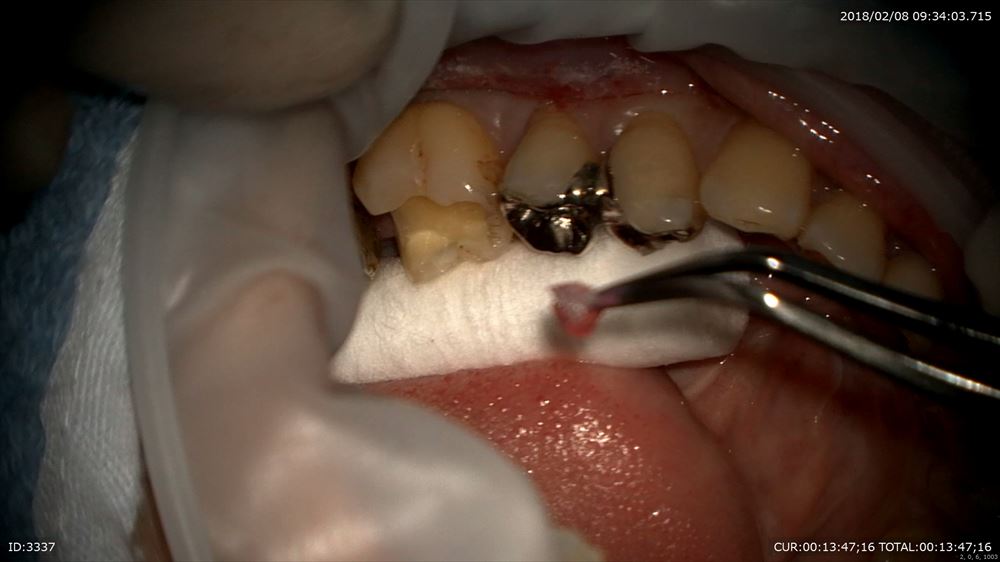

左下

詰め物をオーダーメイド

とにかくやり直しのない治療を目指す為に当院では金属を使用しません。

先程の方もこの方もマイクロスコープを使用し出血がありません。

もちろん無痛。